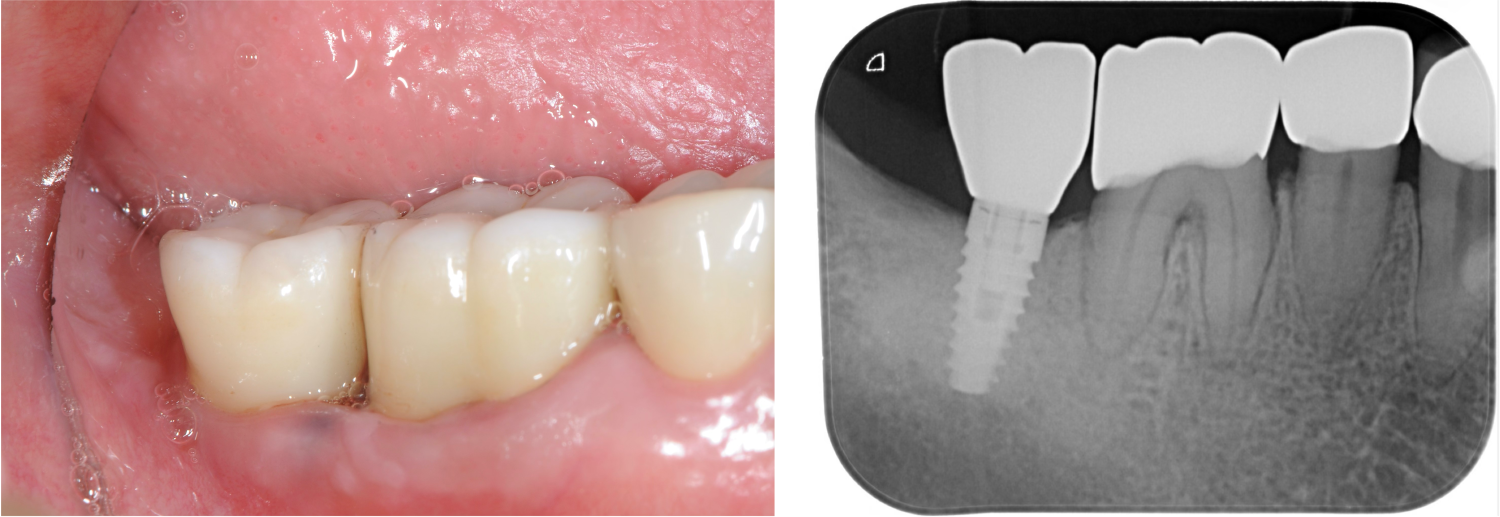

歯周病に罹患した患者さんのインプラント治療の症例①(うえだ歯科)

症例詳細

| 主訴 | 全顎治療希望、奥の歯茎から血が出る、綺麗で噛めるようになりたい |

| 治療内容 | 全顎的に歯周病、歯列不正が認められるため、歯周外科を含む歯周治療、矯正治療、インプラント治療、セラミックによる補綴治療後メインテナンスに移行 |

| 治療費 | 2,930,000円(税込)(インプラントすべて含む) |

| 治療期間 | 2年6ヶ月 |

| 治療回数 | 96回 |

| 想定されたリスク | 歯周病の再発、食いしばり(パラファンクション)によるセラミックの破折、歯の破折 |